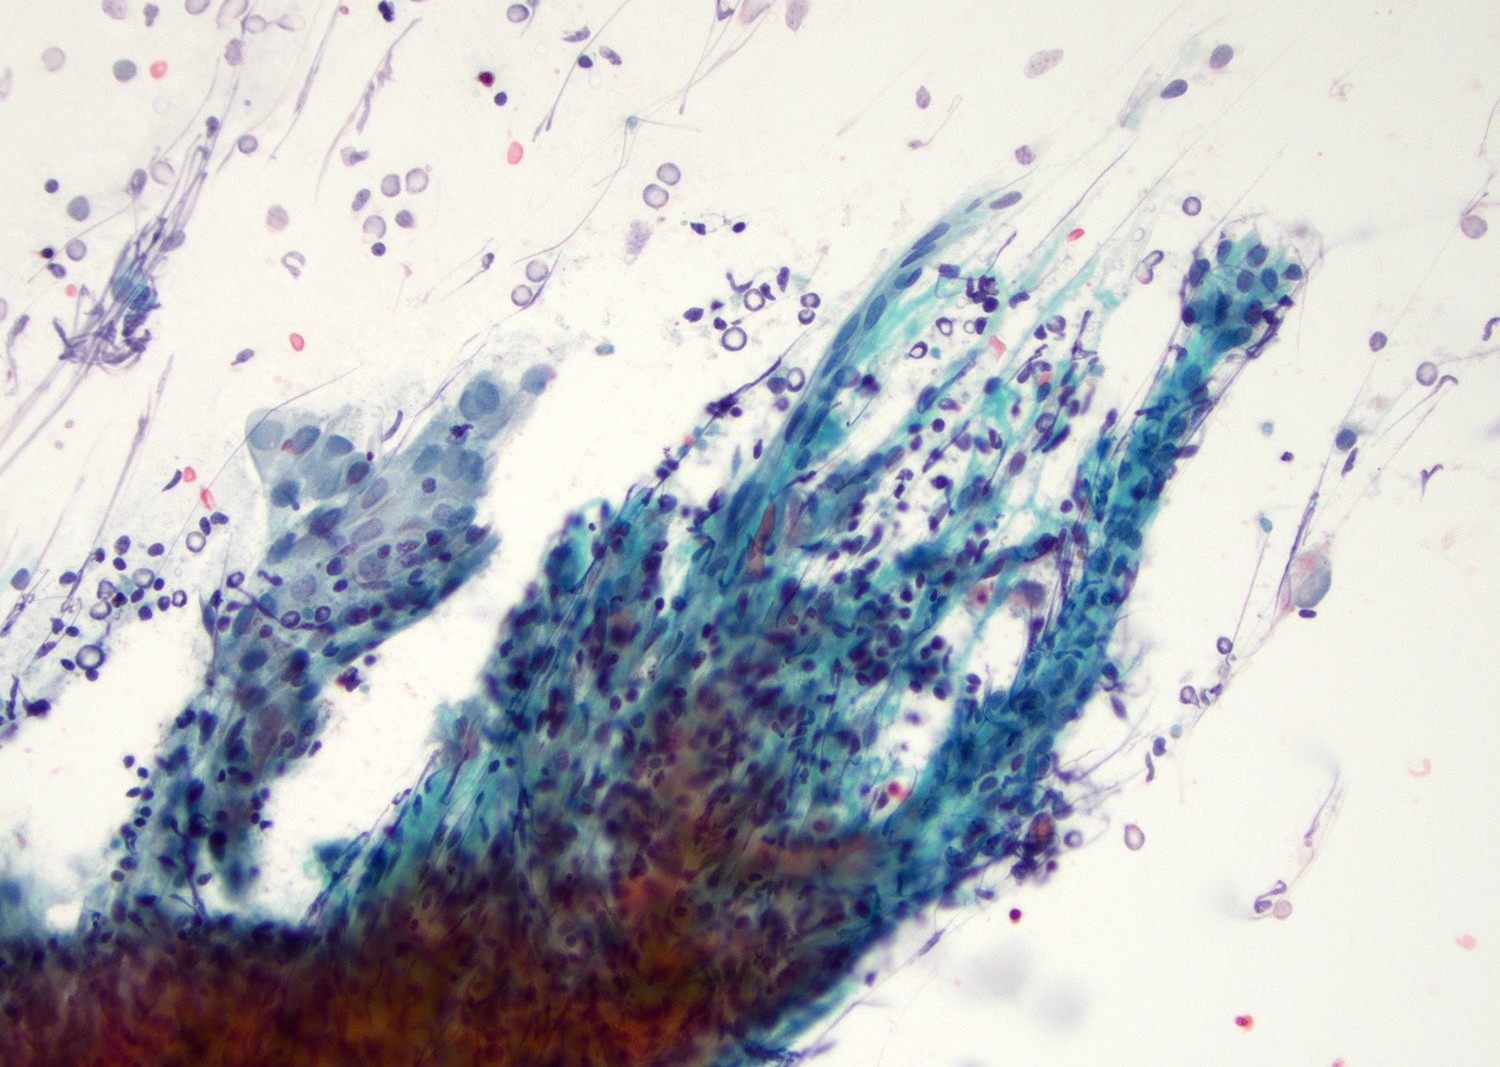

Cytology description

- Mature nucleated squamous cells with variable reactive atypia, anuclear cells and squamous epithelium (Int J Surg Case Rep 2017;41:383, Diagn Cytopathol 2012;40:684)

- Polymorphous lymphocytes and aggregates of epithelioid histiocytes

- Proteinaceous background

- Variable presence of acute inflammation, and bland appearing mucinous ductal cells and ciliated columnar cells

- Scant cellularity, abundant proteinaceous background, lack of squamous cells and epithelial cells, marked atypia of epithelial cells, abundance of lymphocytes pose diagnostic challenges

Cytology images